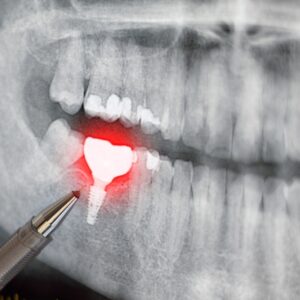

둔산동네비게이션임플란트, 처음이면 알아두어야 할 점은? 안녕하세요. 둔산동네비게이션임플란트 365디지털치과입니다. 치아를 상실한 뒤 임플란트를 고민하게 되는 순간은 대부분 갑작스럽게 찾아옵니다. 갑자기 식사가 불편해지거나, 한쪽으로만 씹게 되는 습관이 생기거나, 시간이 지나면서 주변 치아까지 흔들리는 느낌이 들기도 하는데요. 특히 처음 치료를 고려하는 경우라면 어떤 방식이 나에게 맞는지, 무엇을 기준으로 살펴봐야 하는지 더보기…